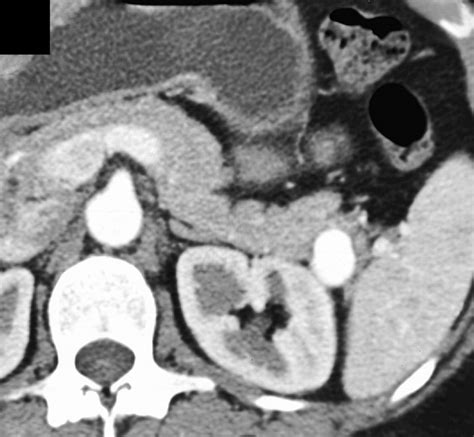

Computed Tomography (CT) Scan: Provides detailed cross-sectional images of the abdomen. It is often used to confirm the presence of an aneurysm and assess its size and location.

• Endovascular Repair: This minimally invasive procedure involves inserting a catheter into a blood vessel, usually in the groin, and guiding it to the site of the aneurysm. A stent or coil is then placed to reinforce the artery and prevent rupture.